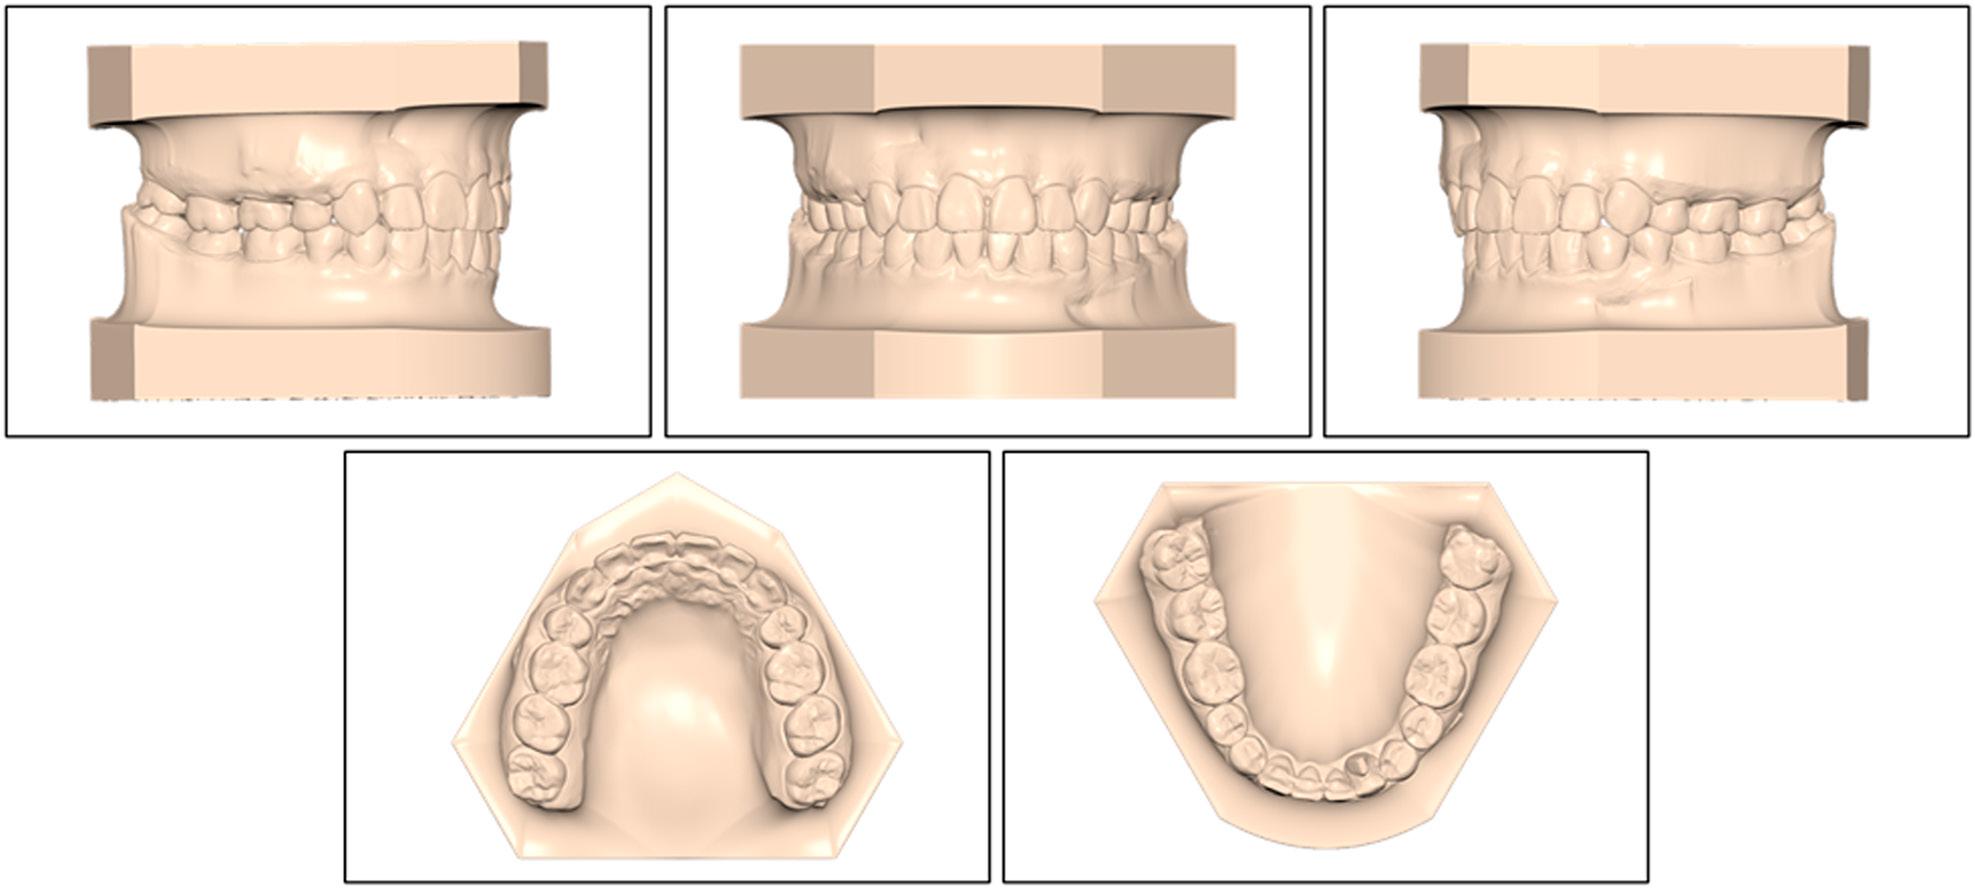

An intra-oral inspection revealed severe maxillary crowding with a 10.8 mm arch-length deficiency (Figure 2). The mandibular arch displayed mild crowding of 2.8 mm, and only four anterior teeth were present. On the left side, an enlarged bifid crown with a pronounced developmental groove was noted, suggesting incomplete fusion of the lateral incisor and canine. On the right side, a single, bulky crown larger than a normal canine and lacking any separation suggested complete fusion of the same tooth pair. Angle molar relationships were Class I bilaterally, and the fused “canine” units also occluded in Class I relationships. The maxillary dental midline co-incided with the facial midline, whereas the mandibular midline deviated 2 mm to the patient’s right.

Pretreatment maxillary and mandibular study models.